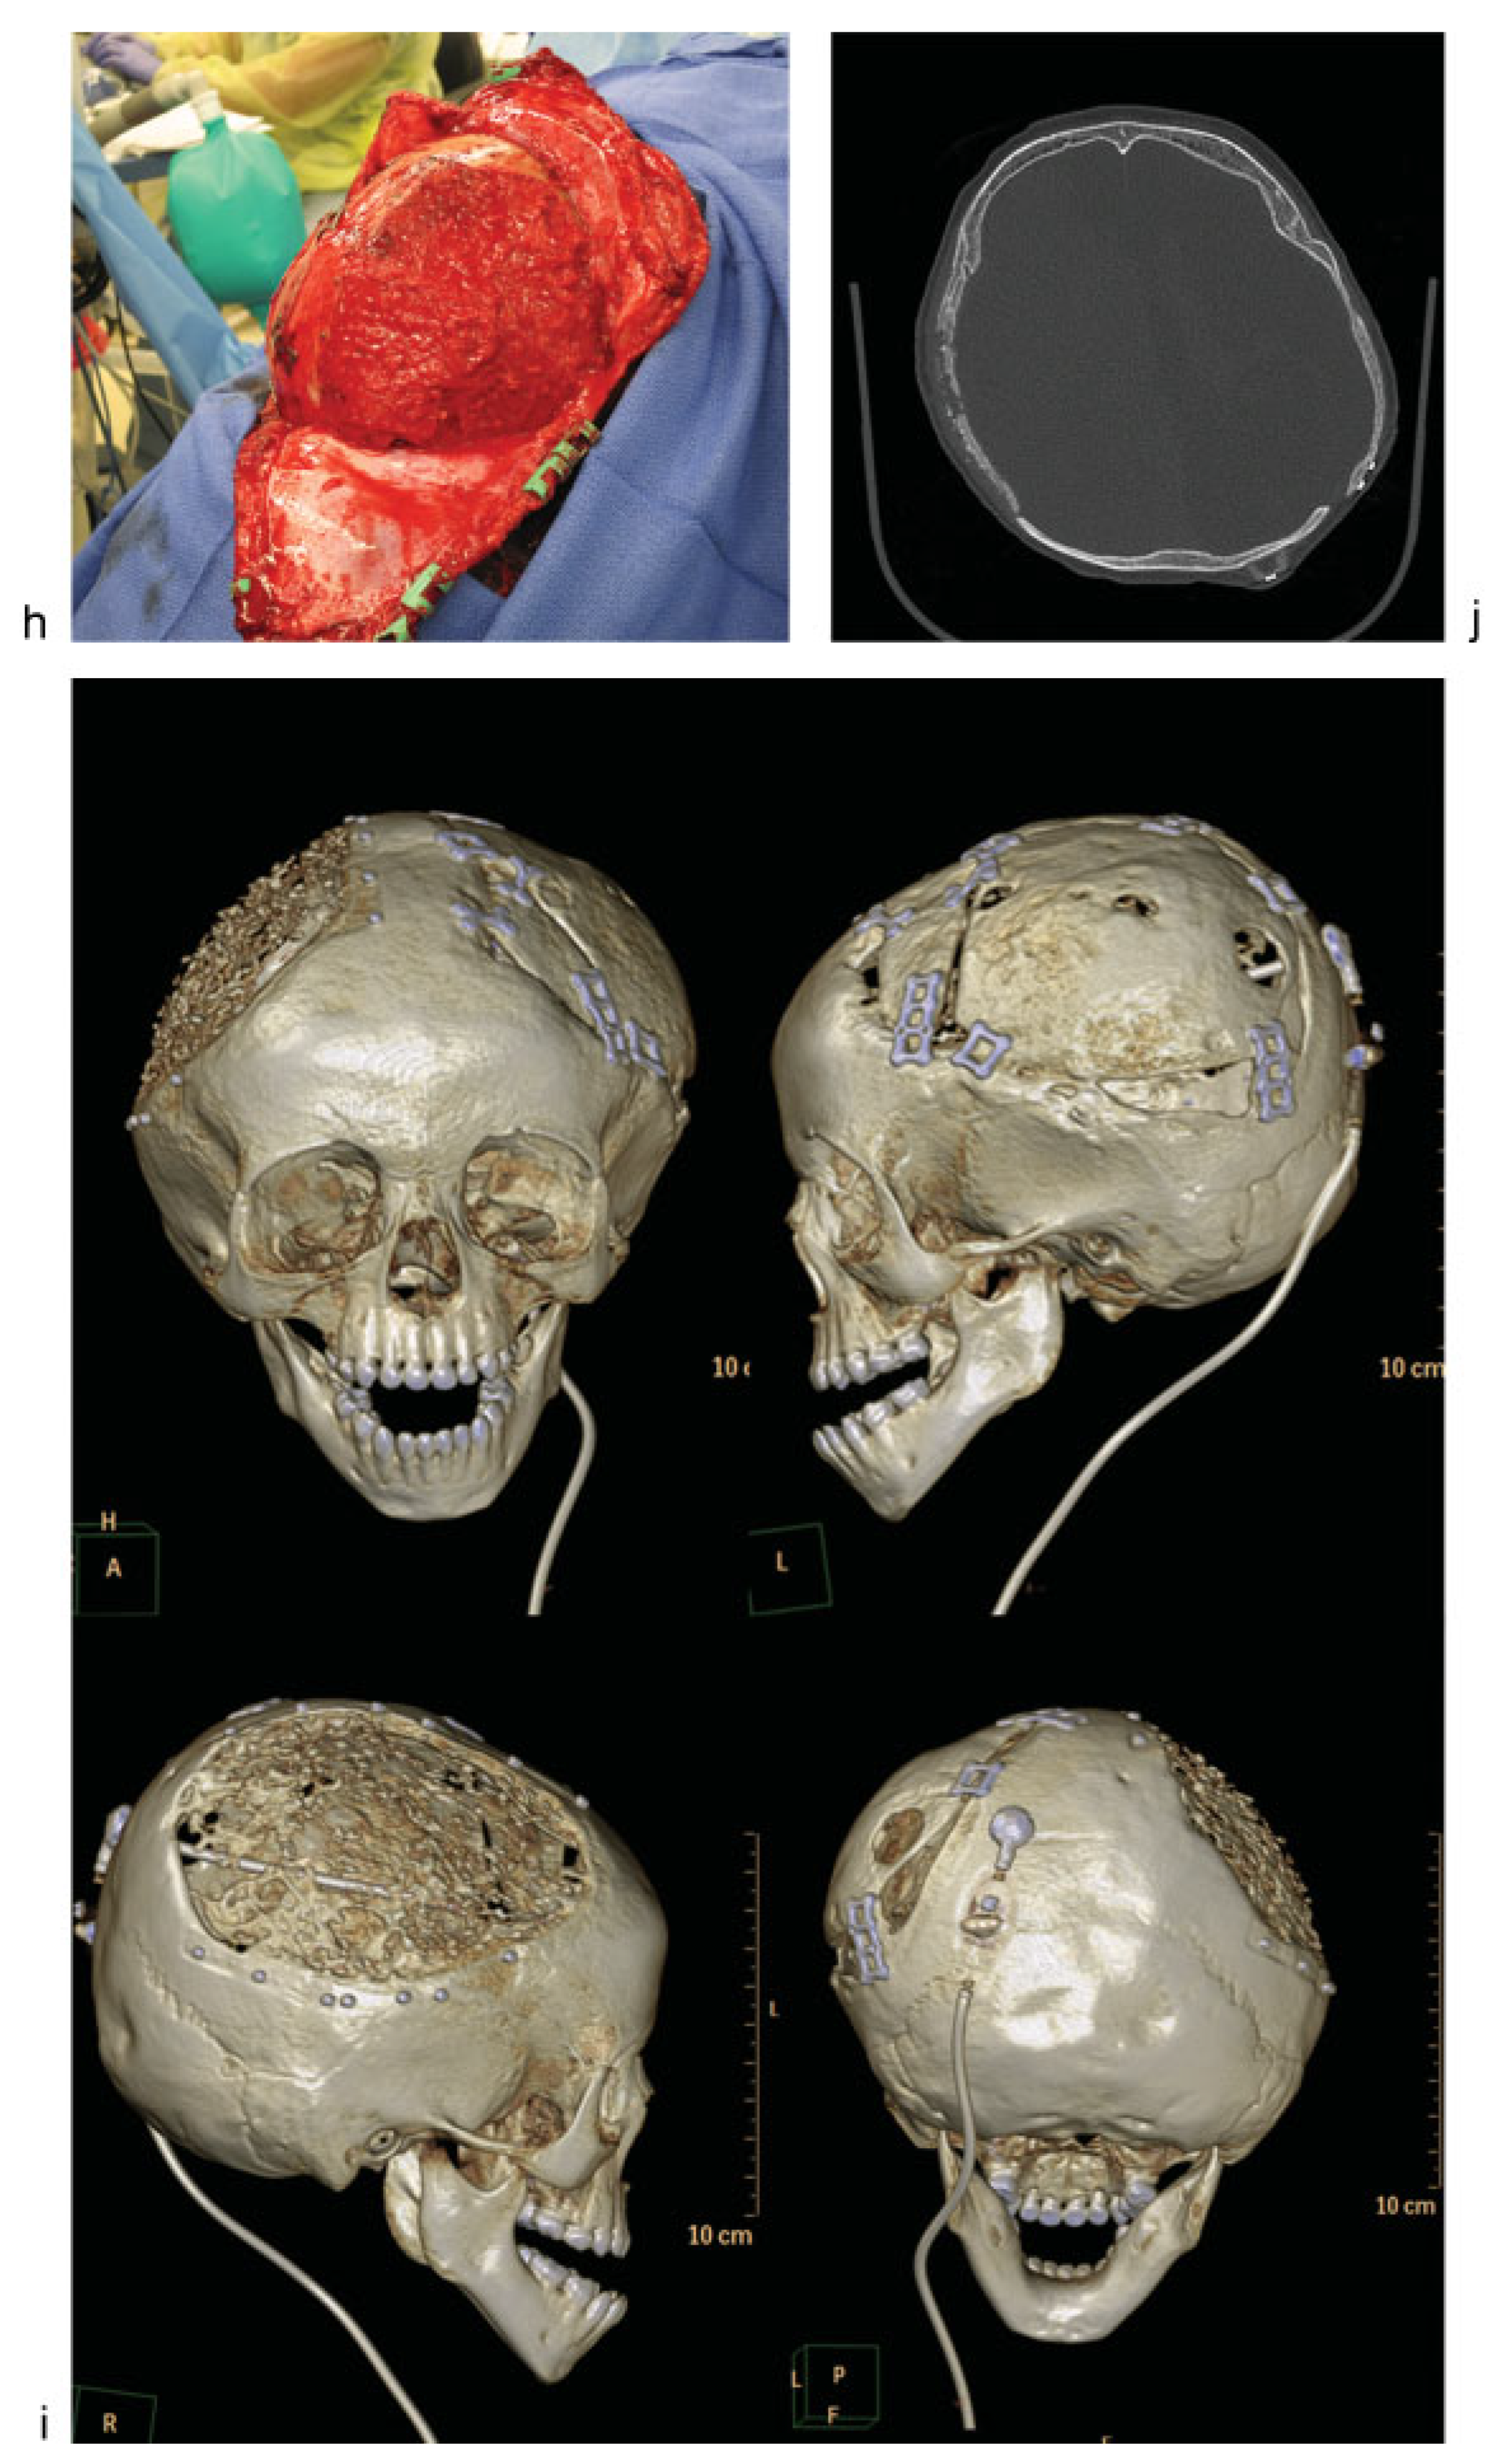

Figure 1.

Case 1: An 18-month-old child with history of decompressive craniectomy for acute traumatic subdural hematoma, with at right frontal ventriculoperitoneal shunt in place for posttraumatic hydrocephalus. The autologous bone flap was retrieved from bone freezer storage and replaced 3 months after the initial trauma to repair the large left frontoparietotemporal skull defect. The autologous cranioplasty failed with bone flap resorption noted 6 weeks later, which was near complete by 4 months after autologous cranioplasty. An exchange cranioplasty was done, with re-siting of the ventriculoperitoneal shunt to the left occipital approach to avoid the bilateral cranioplasty areas. (a) Axial head computed tomographic (CT) scan immediately after autologous cranioplasty (left); axial CT scan of the same patient with bone flap resorption 4 months later (right). (b) Three-dimensional (3D) CT reconstructions showing bone flap resorption and right frontal ventriculoperitoneal shunt in place. (c) Axial CT scan (left) with corresponding intraoperative skull defect (right) at time of second reconstruction (exchange cranioplasty) after bone flap resorption. (d) Exchange cranioplasty. Measuring the donor site for the exchange and templating the cranial defect. (e) Exchange cranioplasty in process after placement of the freshly harvested contralateral bone graft. (f) Harvesting autologous particulates for bone grafting from the inner surface of a full-thickness calvarial flap. (g) Bilaminate mesh cranioplasty: inner layer of mesh in the right frontoparietotemporal calvarial defect, forming the epidural inner cortex. (h) Exchange cranioplasty completed with the recreated “diploic space” in between mesh layers filled autologous particulate bone mixed with demineralized bone matrix and autologous blood, then covered with the outer layer of mesh. (i) 3D CT scan 3 months after exchange cranioplasty showing partial consolidation of particulate graft on the left, incorporation of the full-thickness calvarial graft on the right with good skull contour. The shunt was re-sited to avoid the cranioplasty areas. (j) Axial CTscan 3 months after exchange cranioplasty.

When bone is needed to provide cranial coverage, there are several options if the removed bone is no longer available because of trauma, loss, or infection. These options from the cranium include full-thickness grafts, split-thickness grafts, and particulate bone grafts. These three reconstructive approaches all involve using bone from the healthy parts of the skull to repair the defect and have been shown to have a lower rate of resorption than grafts from elsewhere on the body.[22] Full-thickness calvarial grafts are often used when there is concern about healing, such as, in the cases of the previous failed reconstruction. This approach provides good coverage of the cranial defect but creates a donor site to be repaired. This type of defect can be done using an exchange cranioplasty (Figure 1d, e), in which the existing defect is repaired with the full-thickness calvarial graft, and the donor site is repaired with particulate bone graft harvested from the full-thickness graft. Rogers et al reviewed 20 cases, and found that 15 of 20 had complete healing, and the size of the defects decreased by an average of 96%. This exchange cranioplasty method, although it involves an additional operative site, has been found to be highly effective even for large cranial defects as children have high-osteogenic potential.[23]

Particulate grafts can also be used to repair defects directly. In young children, the supply of autologous bone is limited; particulate grafts can be advantageous as they can be harvested with minimal morbidity (Figure 1f).[24]

Bilaminate constructs with particulate grafts can be made by placing bioresorbable mesh endocranially on the dura, laying in bone particulates mixed with blood, demineralized bone matrix paste and other bone growth enhancing agents, and buttressing with an outer layer of bioresorbable mesh. (Figure 1g, h) This method has been used successfully to augment small and large defects. Chao et al report that all the 11 patients in their initial experience achieved clinically stable reconstructions.[25] This method has the benefit that the donor site returns to full thickness over time. It is best used when the reconstructive site has good healing potential and unscarred dura. Alternatively, an exchange cranioplasty or other reconstructive method may be indicated.[23,26] (Figure 1i, j).